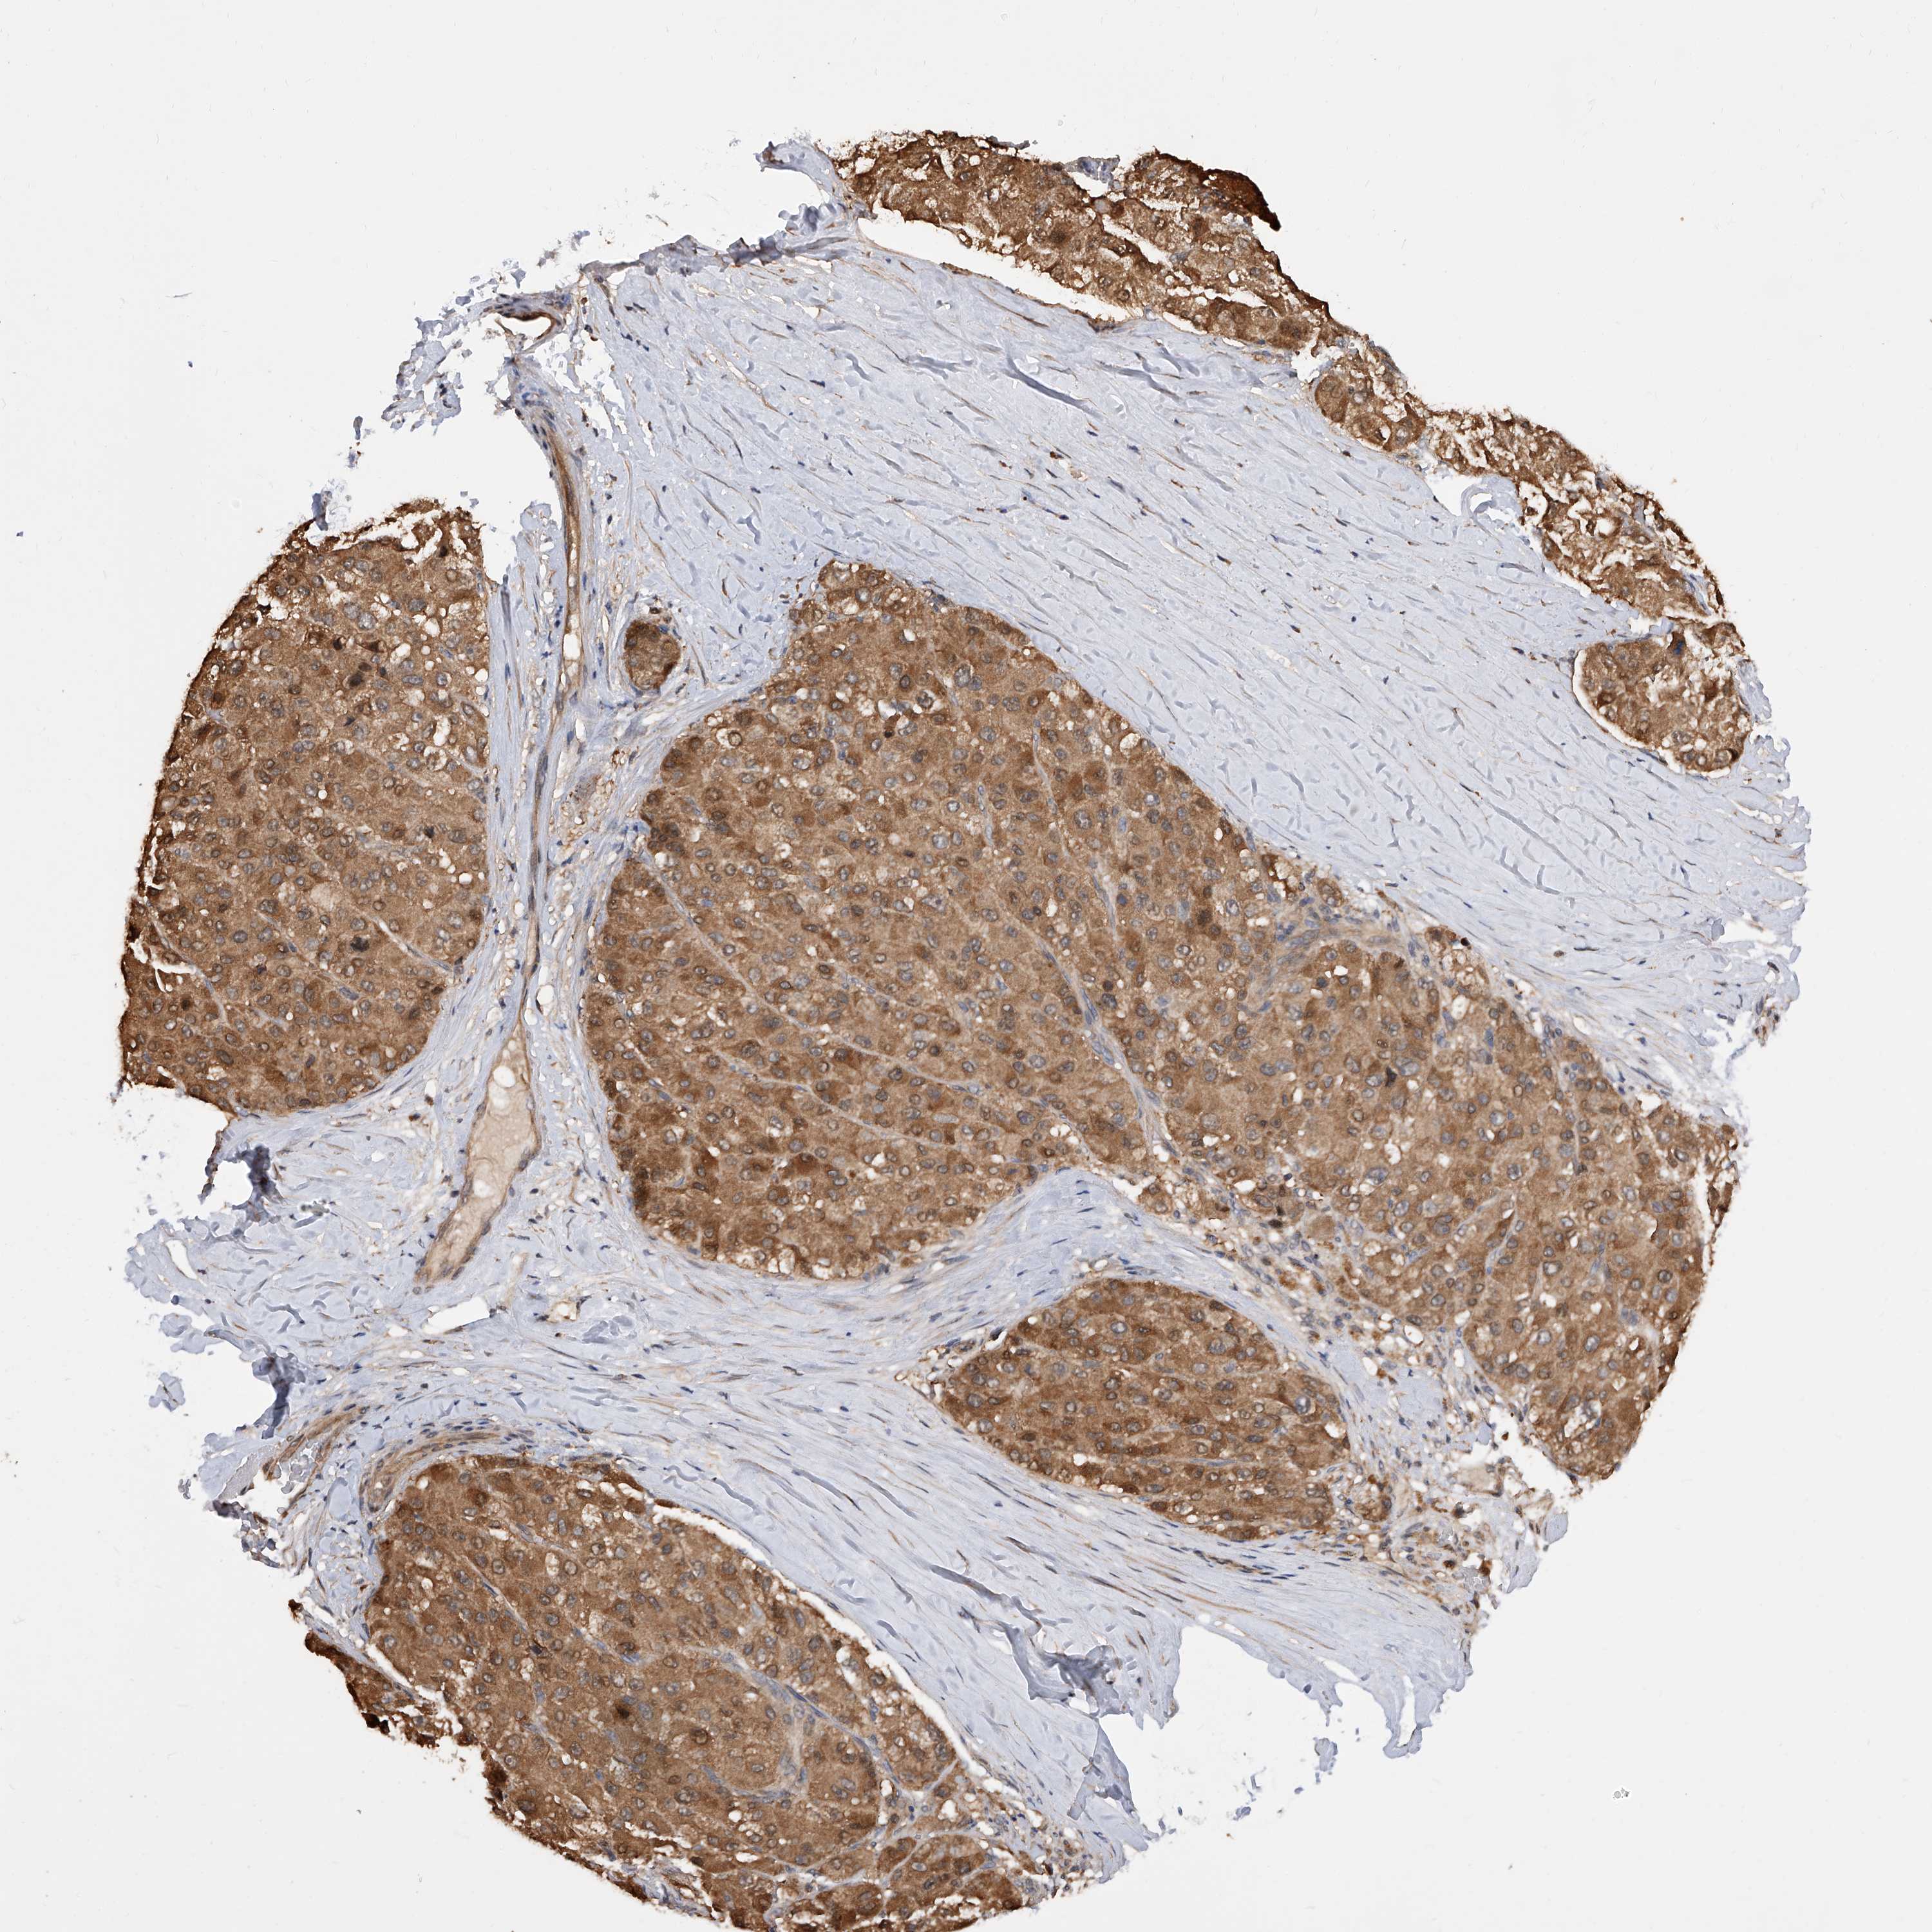

LIVER CANCER - Protein expressioni

A mouse-over function shows sample information and annotation data. Click on an image to view it in a full screen mode. Samples can be filtered based on level of antibody staining by selecting one or several of the following categories: high, medium, low and not detected. The assay and annotation is described here.

Note that samples used for immunohistochemistry by the Human Protein Atlas do not correspond to samples in the TCGA dataset.

Antibody stainingi

Antibody staining in the annotated cell types in the current human tissue is reported as not detected, low, medium, or high, based on conventional immunohistochemistry profiling in selected tissues. This score is based on the combination of the staining intensity and fraction of stained cells.

Each image is clickable and will lead to virtual microscopy that enables deeper exploration of all samples and also displays staining intensity scores, fraction scores and subcellular localization as well as patient and tissue information for each sample.

Antibody HPA031528

Staining

High

Medium

Low

Not detected

Intensity

Strong

Moderate

Weak

Negative

Quantity

>75%

75%-25%

<25%

None

Location

Nuclear

Cytoplasmic/membranous

Cytoplasmic/membranous,nuclear

Cholangiocarcinoma

Carcinoma, Hepatocellular, NOS